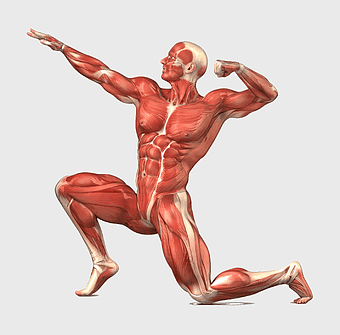

human anatomy diagram, muscular system illustration, human body muscles, fitness anatomy chart, skeletal muscle structure, human physiology study, muscle group analysis -

muscular system illustration, human anatomy diagram, fitness professional figure, skeletal muscle structure, muscular development, human body musculature, anatomical study -